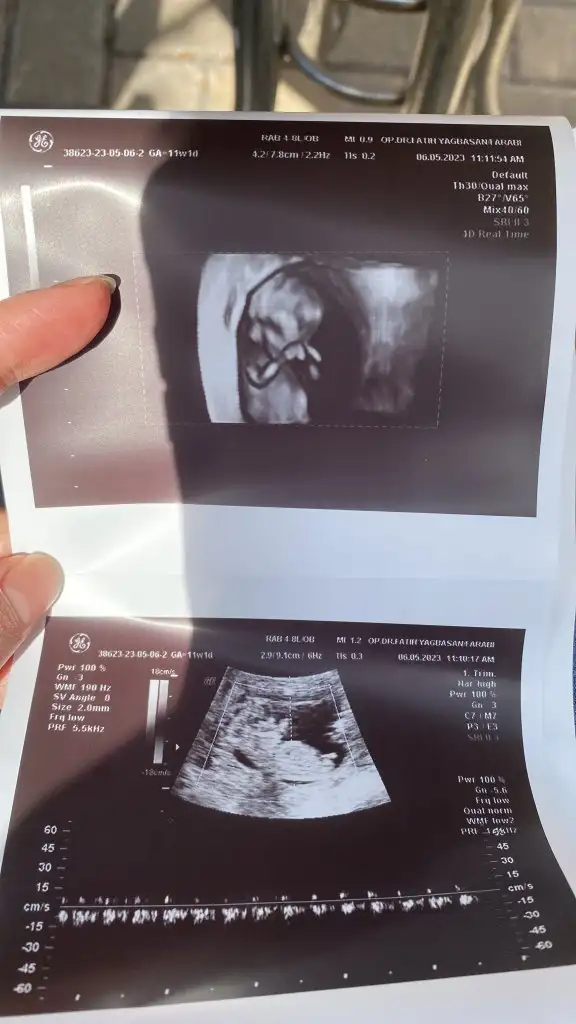

Bugün tam 10 haftalık karından plasentayı da çizdim doktor söyledi orası olduğunu tahminini bekliyorumBurada kaç haftalık? Parlak alan solda gibi eğer karından ultrason ise erkek diye anlıyorum :)

10 haftalık karından bi tahmin alabilir miyiz lütfeeeeenMaşallahsanırım 9 haftalık bana kız gibi geldi ama tamamen öylesine his